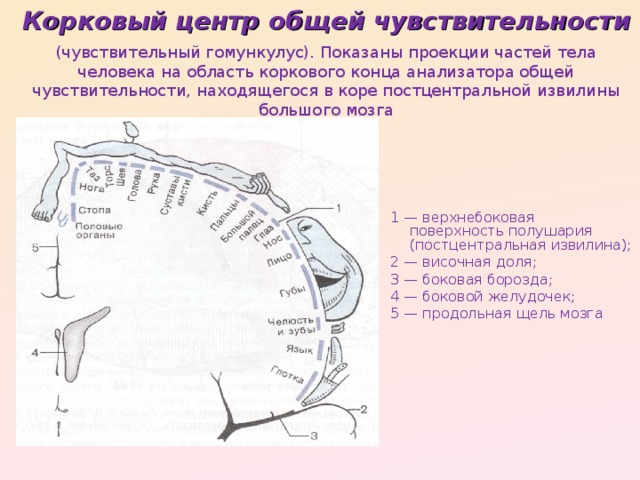

Схема чувствительных зон новой коры мозга